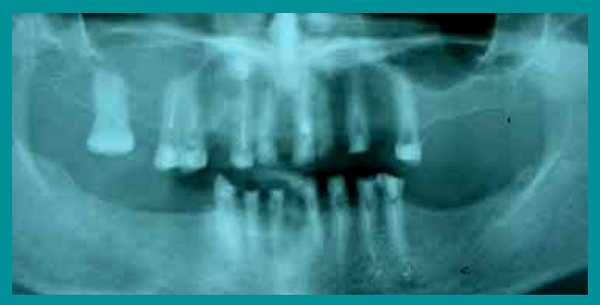

Осмотр выявил очень сильную горизонтальную стираемость верхних и нижних зубов, снижение высоты прикуса и изменение его из нормального в обратный (нижние зубы при смыкании находились впереди верхних). Одновременно на ортопантомограмме височно-нижнечелюстного сустава определялся двухсторонний подвывих нижней челюсти.